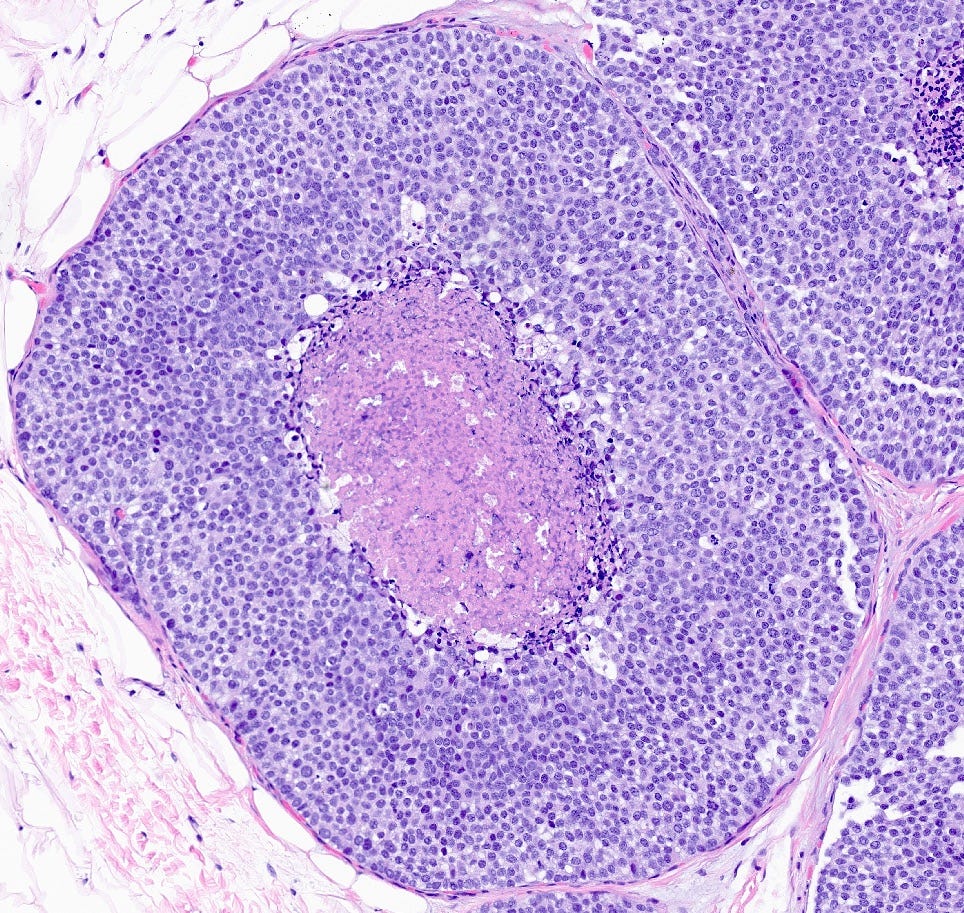

Pleomorphic lobular carcinoma in situ - microscopic images

Pleomorphic LCIS is a rare (< 5% of LCIS) nonclassical or variant form of lobular carcinoma in situ composed of a noninvasive, neoplastic proliferation of large dyscohesive cells with marked nuclear pleomorphism. Its nuclei are > 4 times the size of a lymphocyte and its cytologic features more closely resemble high grade DCIS than classic LCIS. It may exhibit comedonecrosis and calcifications. However, other features overlap with classic LCIS: loss or dysfunction of E-cadherin, cellular dyscohesion, lack of cell polarity, intracytoplasmic lumina, signet ring cells and pagetoid spread. Most cases are associated with classic LCIS and ALH.

Immunostains for E-cadherin may assist in distinguishing LCIS from DCIS although they must be interpreted in the context of the histologic features.

Pleomorphic LCIS accumulates additional alterations and generally exhibits greater genomic instability than classic LCIS.

Pleomorphic LCIS has features of a high risk precursor lesion of invasive carcinoma. It is associated with a high incidence (49%) of associated invasive carcinoma either on core needle biopsy or excision. Treatment consists of surgical excision but there is no consensus on requiring negative margins, adjuvant treatments or sentinel node biopsy.